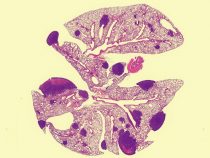

Gén, ktorý sa podieľa na regulácii hladiny cholesterolu, môže rozhodovať aj o tom, či sa rakovina prsníka rozšíri do iných častí tela. Variant génu PCSK9 spôsobuje šírenie rakoviny prsníka. Vedci zistili, že látka, ktorá sa používa na liečbu vysokej hladiny cholesterolu, môže pomôcť zastaviť aj… pokračuj